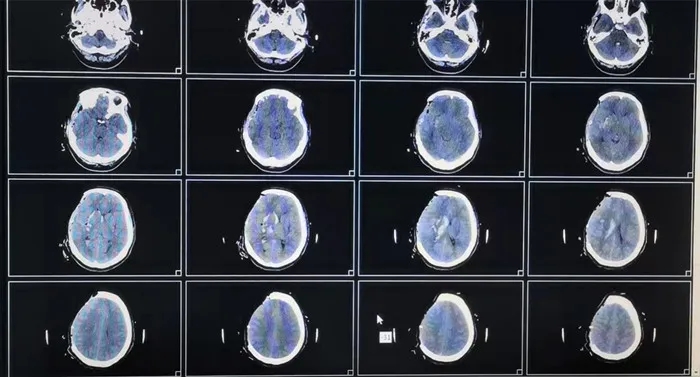

征得小唐家屬同意,神經(jīng)外二科醫(yī)護(hù)團(tuán)隊(duì)凌晨緊急集合,立即為小唐行右側(cè)去骨瓣減壓+血腫清除術(shù)+腦膜擴(kuò)大修補(bǔ)術(shù)。手術(shù)順利結(jié)束,小唐轉(zhuǎn)重癥醫(yī)學(xué)科(ICU)監(jiān)護(hù)治療,術(shù)后進(jìn)一步檢查排除腦動(dòng)脈瘤及腦血管畸形等腦血管病,后病情穩(wěn)定后轉(zhuǎn)入神經(jīng)外二科病房進(jìn)一步治療,目前情況穩(wěn)定,正在康復(fù)中。

術(shù)后影像